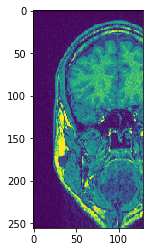

# Alternatively, don't hand over the output image and retrieve it

another_slice = cle.create_2d_xy(input_image)

cle.copy_slice(input_image, another_slice, slice_index = 80)

# show result

cle.imshow(another_slice)

../_images/94d2e1e1937c5fe79debe6f4cc905a8a4f9415fbce9ee61f1b66bdc05012264b.png